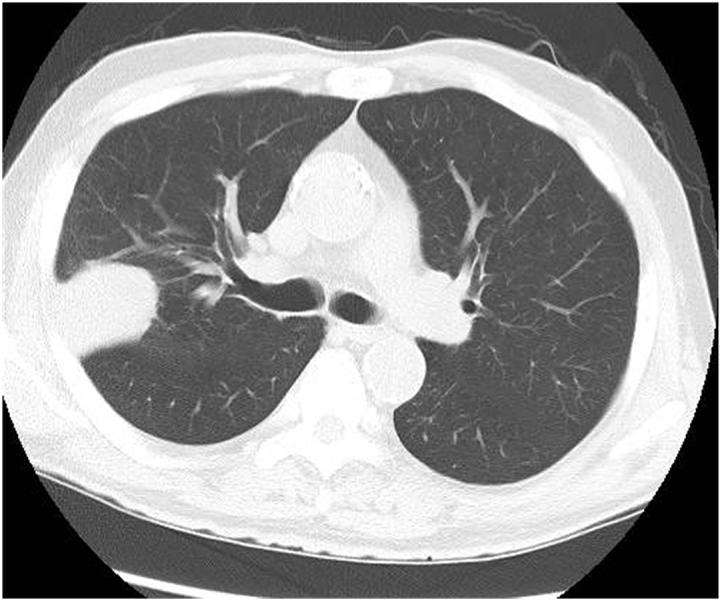

Immune checkpoint inhibitors (ICIs) have been used to treat lung cancer. Several types of ICI-related interstitial lung diseases have been reported, including organizing pneumonia, non-specific interstitial pneumonia, and diffuse alveolar damage. However, pembrolizumab-associated bronchiolitis requiring treatment for persistent cough has not yet been reported. Here, we describe a patient who developed dry cough while being treated with pembrolizumab for lung adenocarcinoma. Radiography and lung biopsy findings indicated bronchiolitis. His cough improved after the discontinuation of pembrolizumab and treatment with erythromycin, an inhaled corticosteroid, a long-acting muscarinic antagonist, and a long-acting β agonist.

免疫检查点抑制剂(ICIs)已被用于治疗肺癌。已有多种ICI相关的间质性肺疾病被报道,包括机化性肺炎、非特异性间质性肺炎和弥漫性肺泡损伤。然而,尚未有关于需要治疗持续性咳嗽的帕博利珠单抗相关细支气管炎的报道。在此,我们描述一名在接受帕博利珠单抗治疗肺腺癌时出现干咳的患者。影像学和肺活检结果显示为细支气管炎。在停用帕博利珠单抗并接受红霉素、吸入性糖皮质激素、长效毒蕈碱拮抗剂和长效β激动剂治疗后,他的咳嗽有所改善。